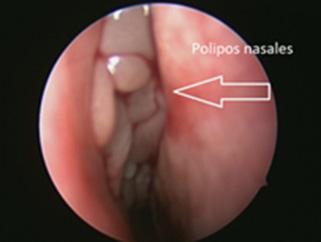

Fracturas nasales Cuerpos extraños intranasales Epistaxis Rinitis Pólipos nasosinusales Rinosinusitis aguda 04 pág. 39 Patología nasosinusal Tumores nasosinusales benignos Tumores nasosinusales malignos